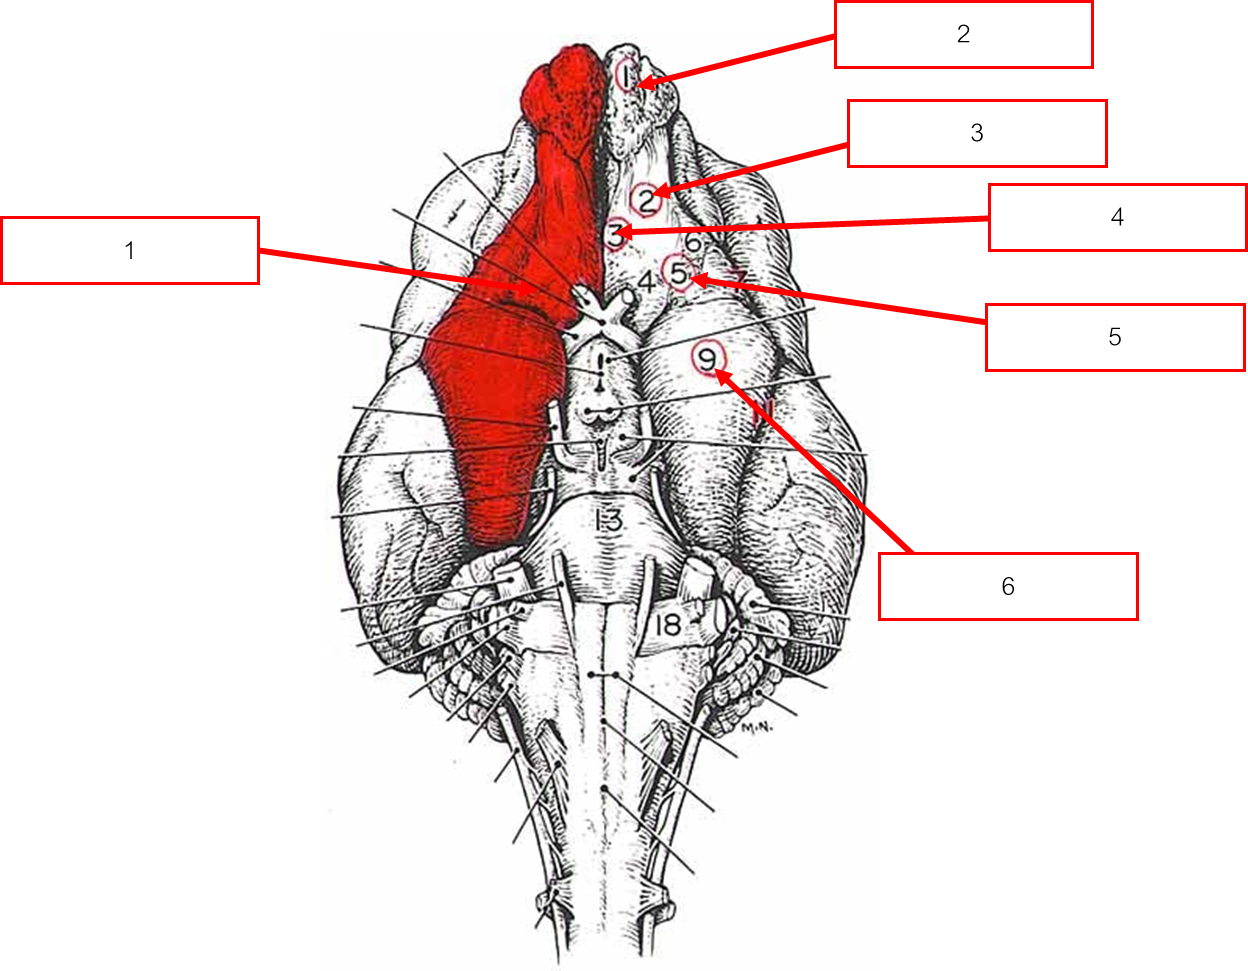

บริเวณ brain stem ด้าน dorsal view

Rostral colliculi

Hippocampus

Fornix

Pineal gland

Thalamus

Fimbria

ก้านสมองด้าน Dorsal view

Hemisphere

Vermis